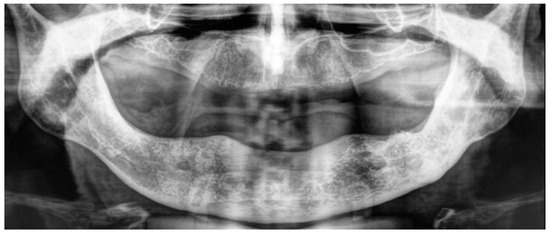

- Explantation of all the nails

- Platelet-Rich Growth Factors (PRGF) were inserted in the residual empty area left from the explantation of the nails and of the related infections.

3.1. Case Report